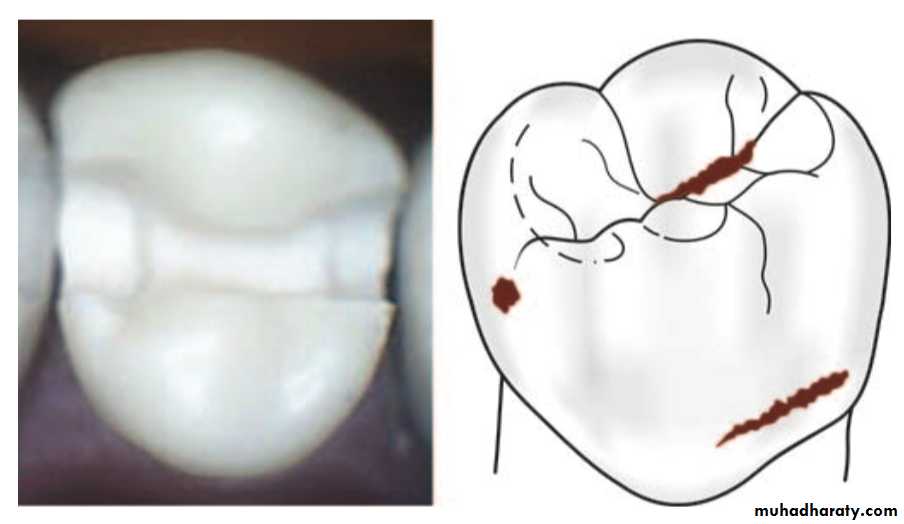

Class II

Preparations on the proximal surface of premolars and molars are class IIModification of Black’s classification was made to provide more specific localization of preparations.

Class II–Preparations on the single or both proximal surface of premolar and molar teeth. When there is involvement of both proximal surfaces, it is called mesio- occluso-distal (MOD) preparation